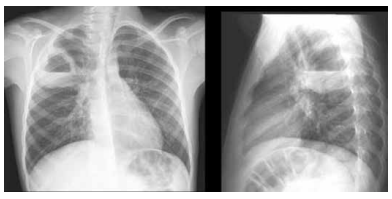

Um idoso de 76 anos de idade, em reabilitação neurológica devido a um hematoma subdural, após sofrer queda da própria altura, em uso de gastrostomia (passada em internação prolongada recente há menos de uma semana), dirigiu-se ao pronto-socorro, trazido pela família e proveniente de instituição de reabilitação para idosos. O paciente foi trazido devido a um quadro de febre, à confusão mental e à dispneia já há três dias. Foi realizada radiografia de tórax na admissão, cujas imagens estão dispostas a seguir.

Com base nessa situação hipotética, assinale a alternativa que apresenta a hipótese diagnóstica adequada.